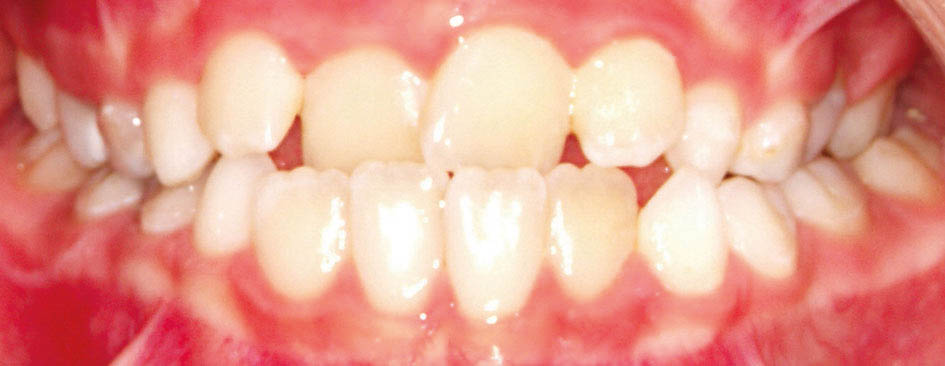

برای نگهدارنده به میزان اوربایت بیمار نگاه میکنیم. زمانی که اوربایت مناسب است (شکل 29-5) نیاز به نگهدارنده نداریم و خود دندانهای قدامی پایین مانع ریلاپس درمان میشود. اگر اوربایت کم باشد میتوانید از سیم twisted روی دندانهای انسیزور بالا که با کامپوزیت میچسبانید استفاده نمایید (شکل 30-5).

شکل 29-5: اصلاح کراس قدامی و داشتن اوربایت مناسب